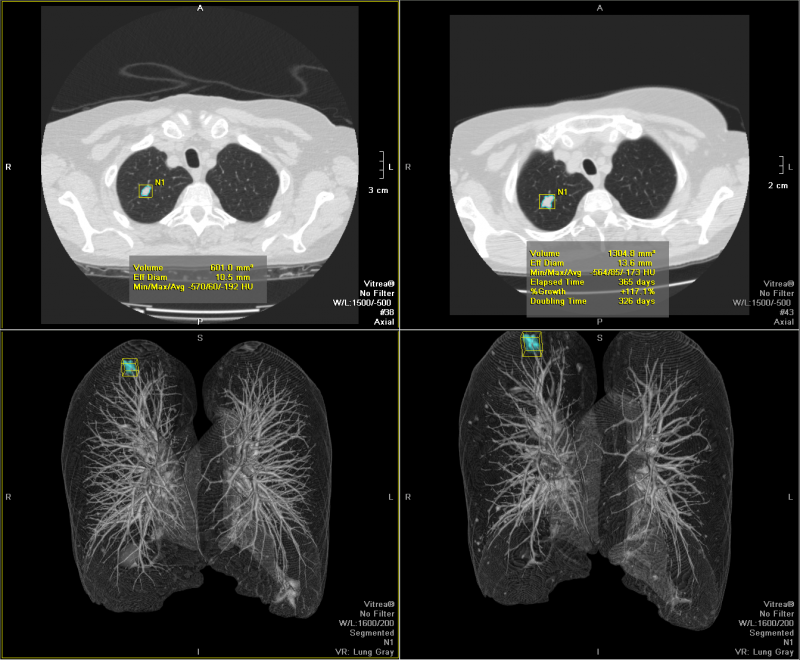

VitreaTM 產(chǎn)品為醫(yī)師提供處理分析2D, 3D和4D醫(yī)學(xué)影像的全套工具, 同時支持多種 設(shè)備 - CT, MR, XA, PET, US, SPECT. 特別在心臟科, 神經(jīng)科, 腫瘤科與介入治療方面 提供了豐富而有針對性的應(yīng)用, 為醫(yī)療專家在手術(shù)計劃與救治病患時提供更多幫助.